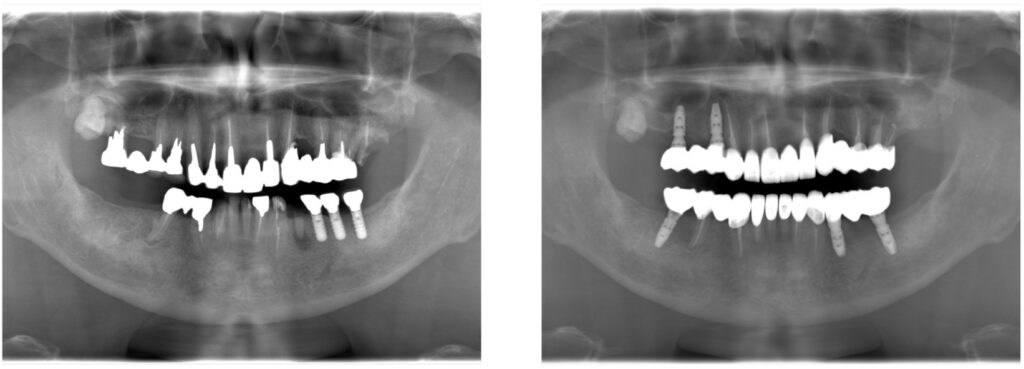

ご自身の大切な歯を失ってしまった場合にはインプラント治療が有効な治療のうちの一つです。当院では精密な歯科治療で歯を削らないように心がけていますが、外傷や歯周病、虫歯などで歯を失ってしまった方には天然の歯とほぼ同等の噛む力を取り戻せるインプラント治療もおすすめしています。

歯を失ってしまっても健やかな生活を送れるように、第2の永久歯ともいわれているインプラント治療で人工歯を装着するサポートを当院でいたします。インプラント治療で不安に感じている方もご安心ください。メリットとデメリットも含めて丁寧にご説明させていただき患者さまに寄り添った治療をしていきます。

インプラントとは、歯が無い顎の骨に人工歯根を埋め込み、それを土台にしてセラミックの歯を装着する治療です。

顎の骨に固定した人工歯根を固定するため、自分の歯のように食事をすることができ、見た目も自然に仕上がるので第2の永久歯とも呼ばれています。従来のブリッジ・入れ歯などの治療法とは違い、歯根も取り戻すことができるのが特徴です。しかし、歯根を埋め込むので手術が必要になるというデメリットもあります。